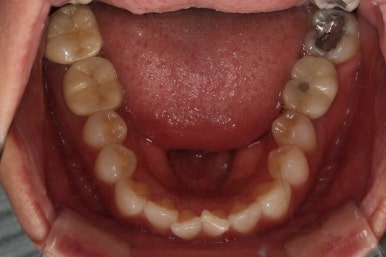

전후 사진을 비교해 볼게요.

6개월만에 부산부분치아교정 완료했어요.

치열도 가지런해졌고, 웃는 모습도 매우 좋아졌네요.

이상 미니스크류, 미니튜브 등을 이용해 앞니를 부산부분치아교정 했던 치료사례였습니다.